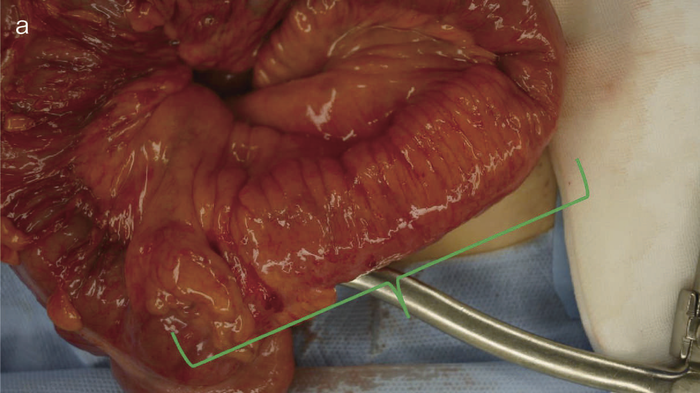

図34 術前CT

術前CTでは回腸末端の壁肥厚を認め,周囲リンパ節の腫大は明らかではなかった。

術中所見では,肝転移,腹膜播種はなく,回盲部周囲のリンパ節には軽度の腫大を認めたものの,明らかな転移を疑う所見はなかった。回腸末端部に回盲弁から連続した壁硬化とfat creepingを伴う病変を認めた(図35a緑の範囲)。回結腸動脈が主な支配血管であり,触診上壁の硬化を認めた部から口側に5 cmまでの回腸と上行結腸を切除した。術中,迅速病理診断で202リンパ節に転移がないことを確認し,回結腸動脈根部まで郭清した。

図36 切除標本

切除標本の肉眼像では4 cm長の全周性腫瘍でvillous様の構造を呈しており,この肛門側に縦走潰瘍を伴う5 cm長の病変(炎症)を認めた。

病理組織検査所見では,well differentiated adenocarcinoma,m,ly0,v0,pN0,p53弱陽性,全層性炎症で非乾酪性類上皮性肉芽腫を認め,診断後の経過は短いものの,CDの慢性炎症から生じた炎症性発癌と考えられた。

CD腸管癌では周囲病変と癌あるいはdysplasiaの範囲を区別することは困難で,本症例のように切除範囲が長くなる場合もあり得る。